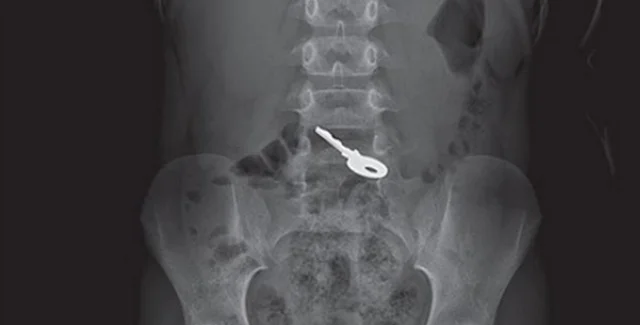

Шестилетний ребенок проглотил ключ | Фото: Jam Press

Несмотря на отсутствие физических симптомов, в приемном отделении был проведен рентген, который показал инородное тело в животе. Поскольку ключ не вызвал осложнений, медики решили не проводить операцию, а ограничиться наблюдением.

Специалисты регулярно делали рентген, чтобы отследить перемещение объекта. Через 48 часов снимки показали, что ключ уже добрался до кишечника.